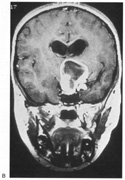

Fig. 15. Bilateral incomplete hemianopia. A 69-year-old man with decreased vision after prostate surgery. A. Fields show remaining central parafoveal vision with some sparing of inferior left quadrant. Note how the defect respects the vertical meridian. B. MRI shows bilateral medial occipital infarction, with sparing of the occipital poles, accounting for the macular-sparing bilaterally. (Courtesy of Dr. Lucia Vaina.)